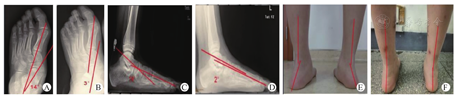

行跟腱延长及内侧组织紧缩术后需石膏固定4周,术后行直腿抬高锻炼及膝关节和足趾的主动活动;未行软组织手术或进行腓肠肌松解的可不行石膏固定,夜间佩戴行走支具,术后第一天行患侧踝关节的被动屈伸功能锻炼。术后第二天行患侧踝关节的主动屈伸功能锻炼。术后第12~14天拆线。术后第六周开始部分负重功能锻炼,以能忍受的疼痛为度。术后即刻、6、12周行患足正侧斜位X线片检查,之后每2~3个月检查一次,观察畸形矫正及内植物位置情况(图1)。末次随访时测量Meary角及正位片第一跖距角与术前相应角度进行统计学比较,采用AOFAS踝-后足评分及VAS评分标准对患足功能进行评估[4]。

对术后18例(20侧足)患儿随访18~36个月,平均25.3个月。伤口均Ⅰ期愈合,无感染。1侧足术后3个月由于过度活动及扭伤出现距下关节制动器脱出,故再次手术置入距下关节制动器后患儿疗效满意。其余患儿随访期间无制动器松动、脱出,平足畸形复发等并发症发生。术后患足疼痛明显减轻,足弓塌陷明显改善。末次随访时Meary角由术前的(17.5°±4.4°)改善为术后(4.1°±1.2°)(P<0.05),X线正位片第一跖距角由术前的(15.3°±3.1°)改善为术后(4.8°±1.3°)(P<0.05),AOFAS踝-后足评分由术前的(66.6±5.8)分改善为术后(88.6±7.9)分(P<0.05),VAS评分由术前的(6.6±0.6)分改善为术后(1.7±0.3)分(P<0.05)。